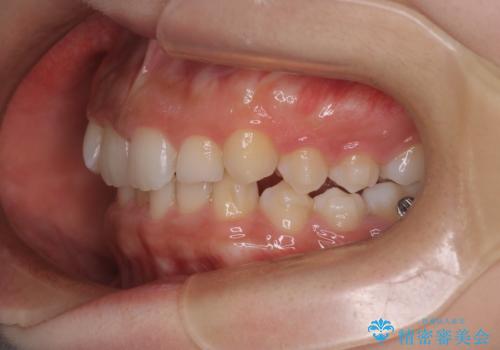

- 患者様は、ディープバイト(深い噛み合わせ)と、咬合平面の左下がりが気になるとのことでご来院されました。診断の結果、非抜歯で治療可能と判断し、透明なマウスピース型矯正装置「インビザライン」を用いる方針としました。治療では、歯列全体の調整を行いながら、咬合平面の水平化を重点的に進める計画を立案しました。2年間で計画的にマウスピースを交換し、左右のバランスと噛み合わせの改善を目指しました。

ディープバイトの矯正は、噛み合わせが深くなりがちなため、細心の注意を払いながら進める必要があります。本症例では、奥歯の高さを調整しつつ前歯の噛み合わせを浅くすることで、全体の咬合バランスを整えました。また、咬合平面の左下がりを修正する過程で、歯列に不均等な力がかからないよう、インビザラインのアタッチメント配置を最適化しました。患者様には装着時間を守っていただき、治療が計画通り進むよう協力をお願いしました。治療終了後には、リテーナーを装着して安定性を確保しました。